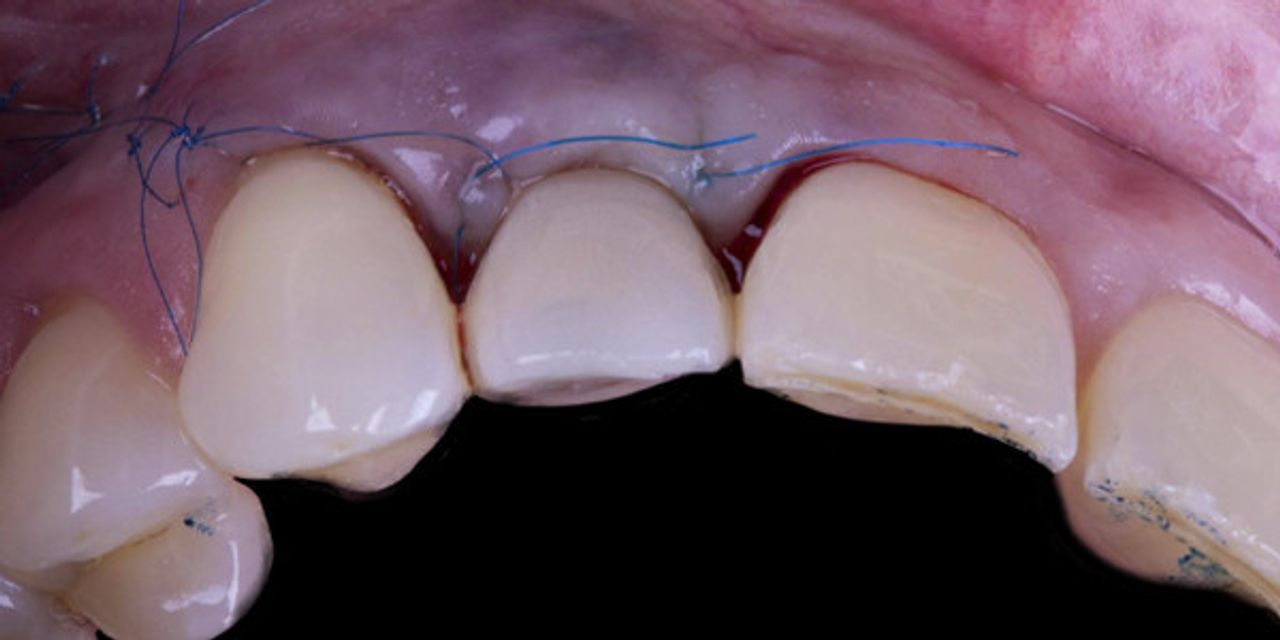

Implant-Perio Evolution 2.0. Протокол винирной реконструкции: пошаговое использование в эстетической зоне

- Минимально инвазивные методики удаления зубов.

- Инструменты для минимально инвазивного удаления

- Сложное удаление зубов без откидывания лоскута

- Использование Socket grafting

- Выбор материала для графтинга

- Работа с участками костной ткани после удаления зубов с целью минимизации потери контура альвеолярного гребня

- Концепция восстановительной регенерации тканей (RDTR)

- Размещение и направление имплантатов в место экстракции зуба

- Размещение костного материала в место экстракции зуба